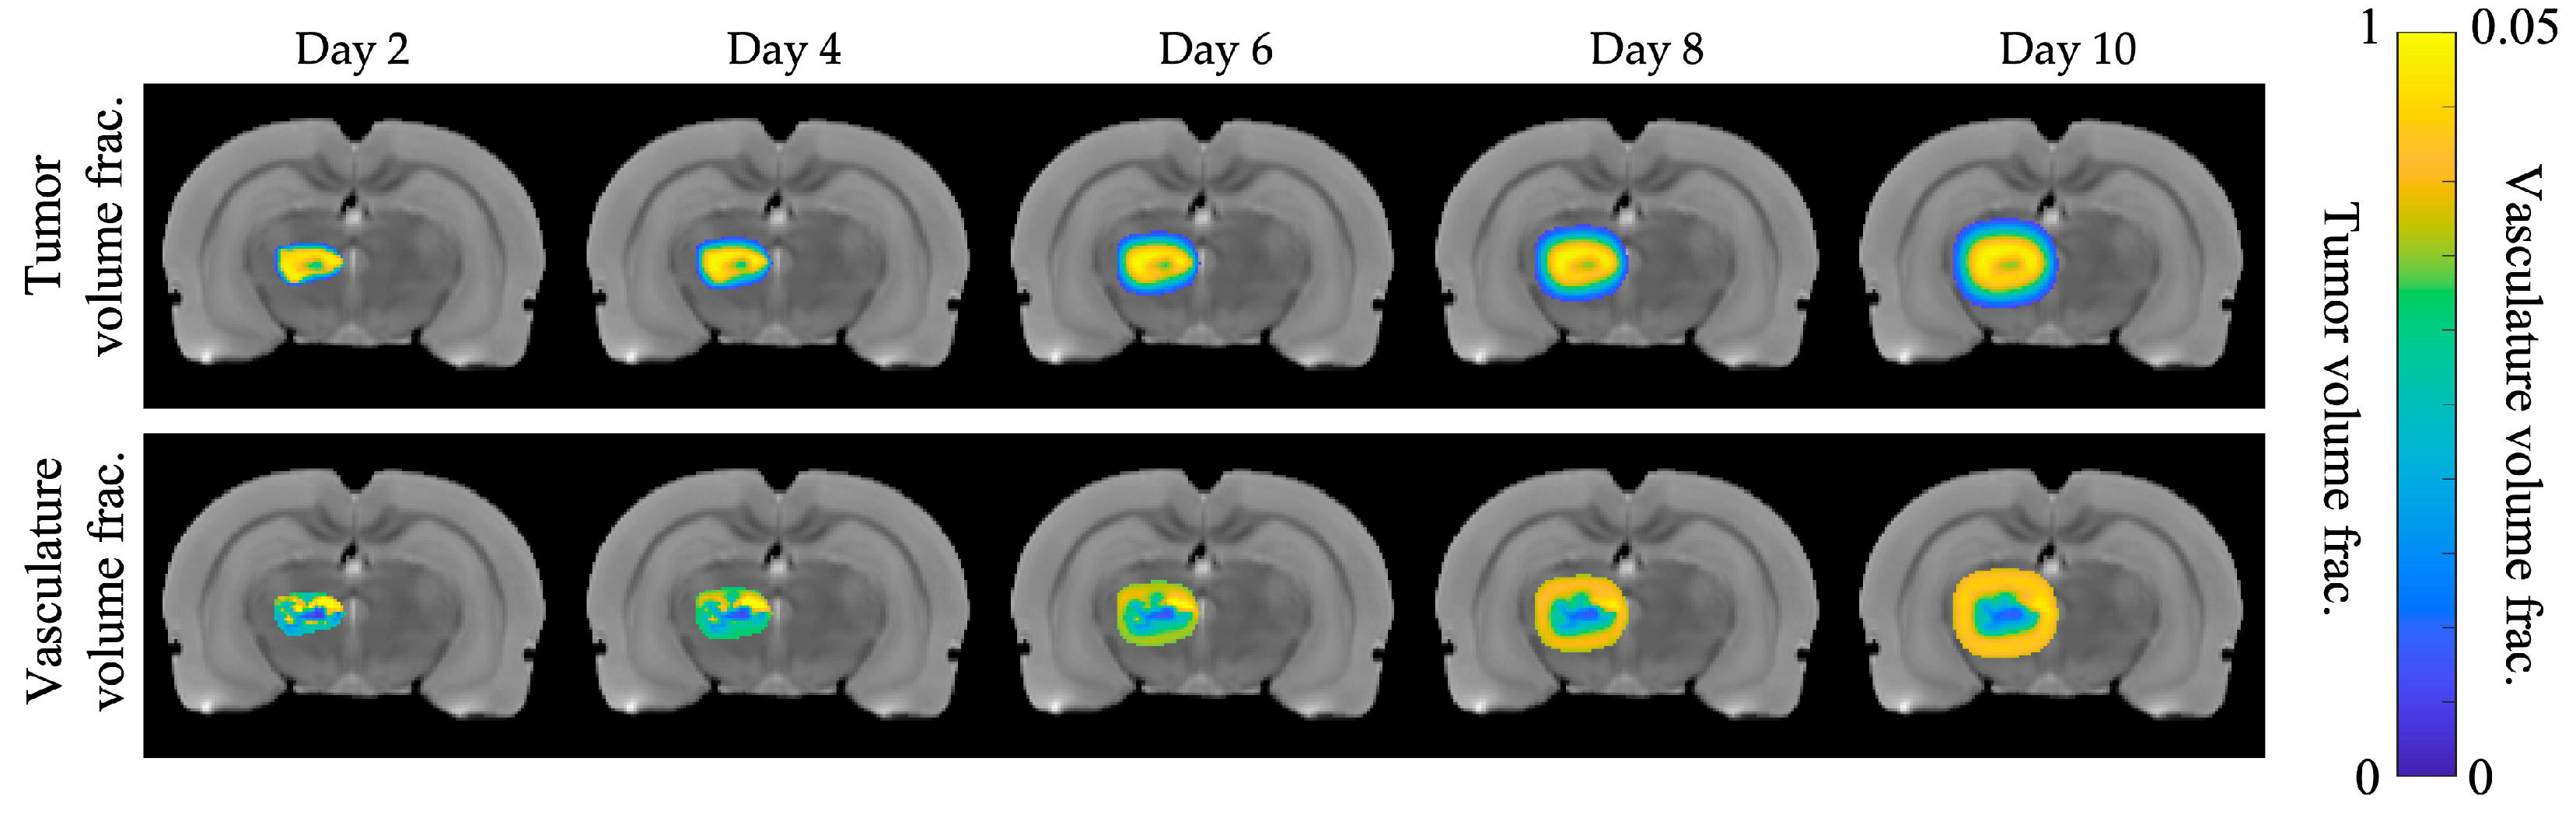

3.1. Representative Ground Truth Images

| Nt(x,t) | fraction of tumor cells per voxel | Initialized at Day 1 with murine DW-MRI data |

| Nv(x,t) | fraction of vasculature per voxel | Initialized at Day 1 with murine DCE-MRI data |